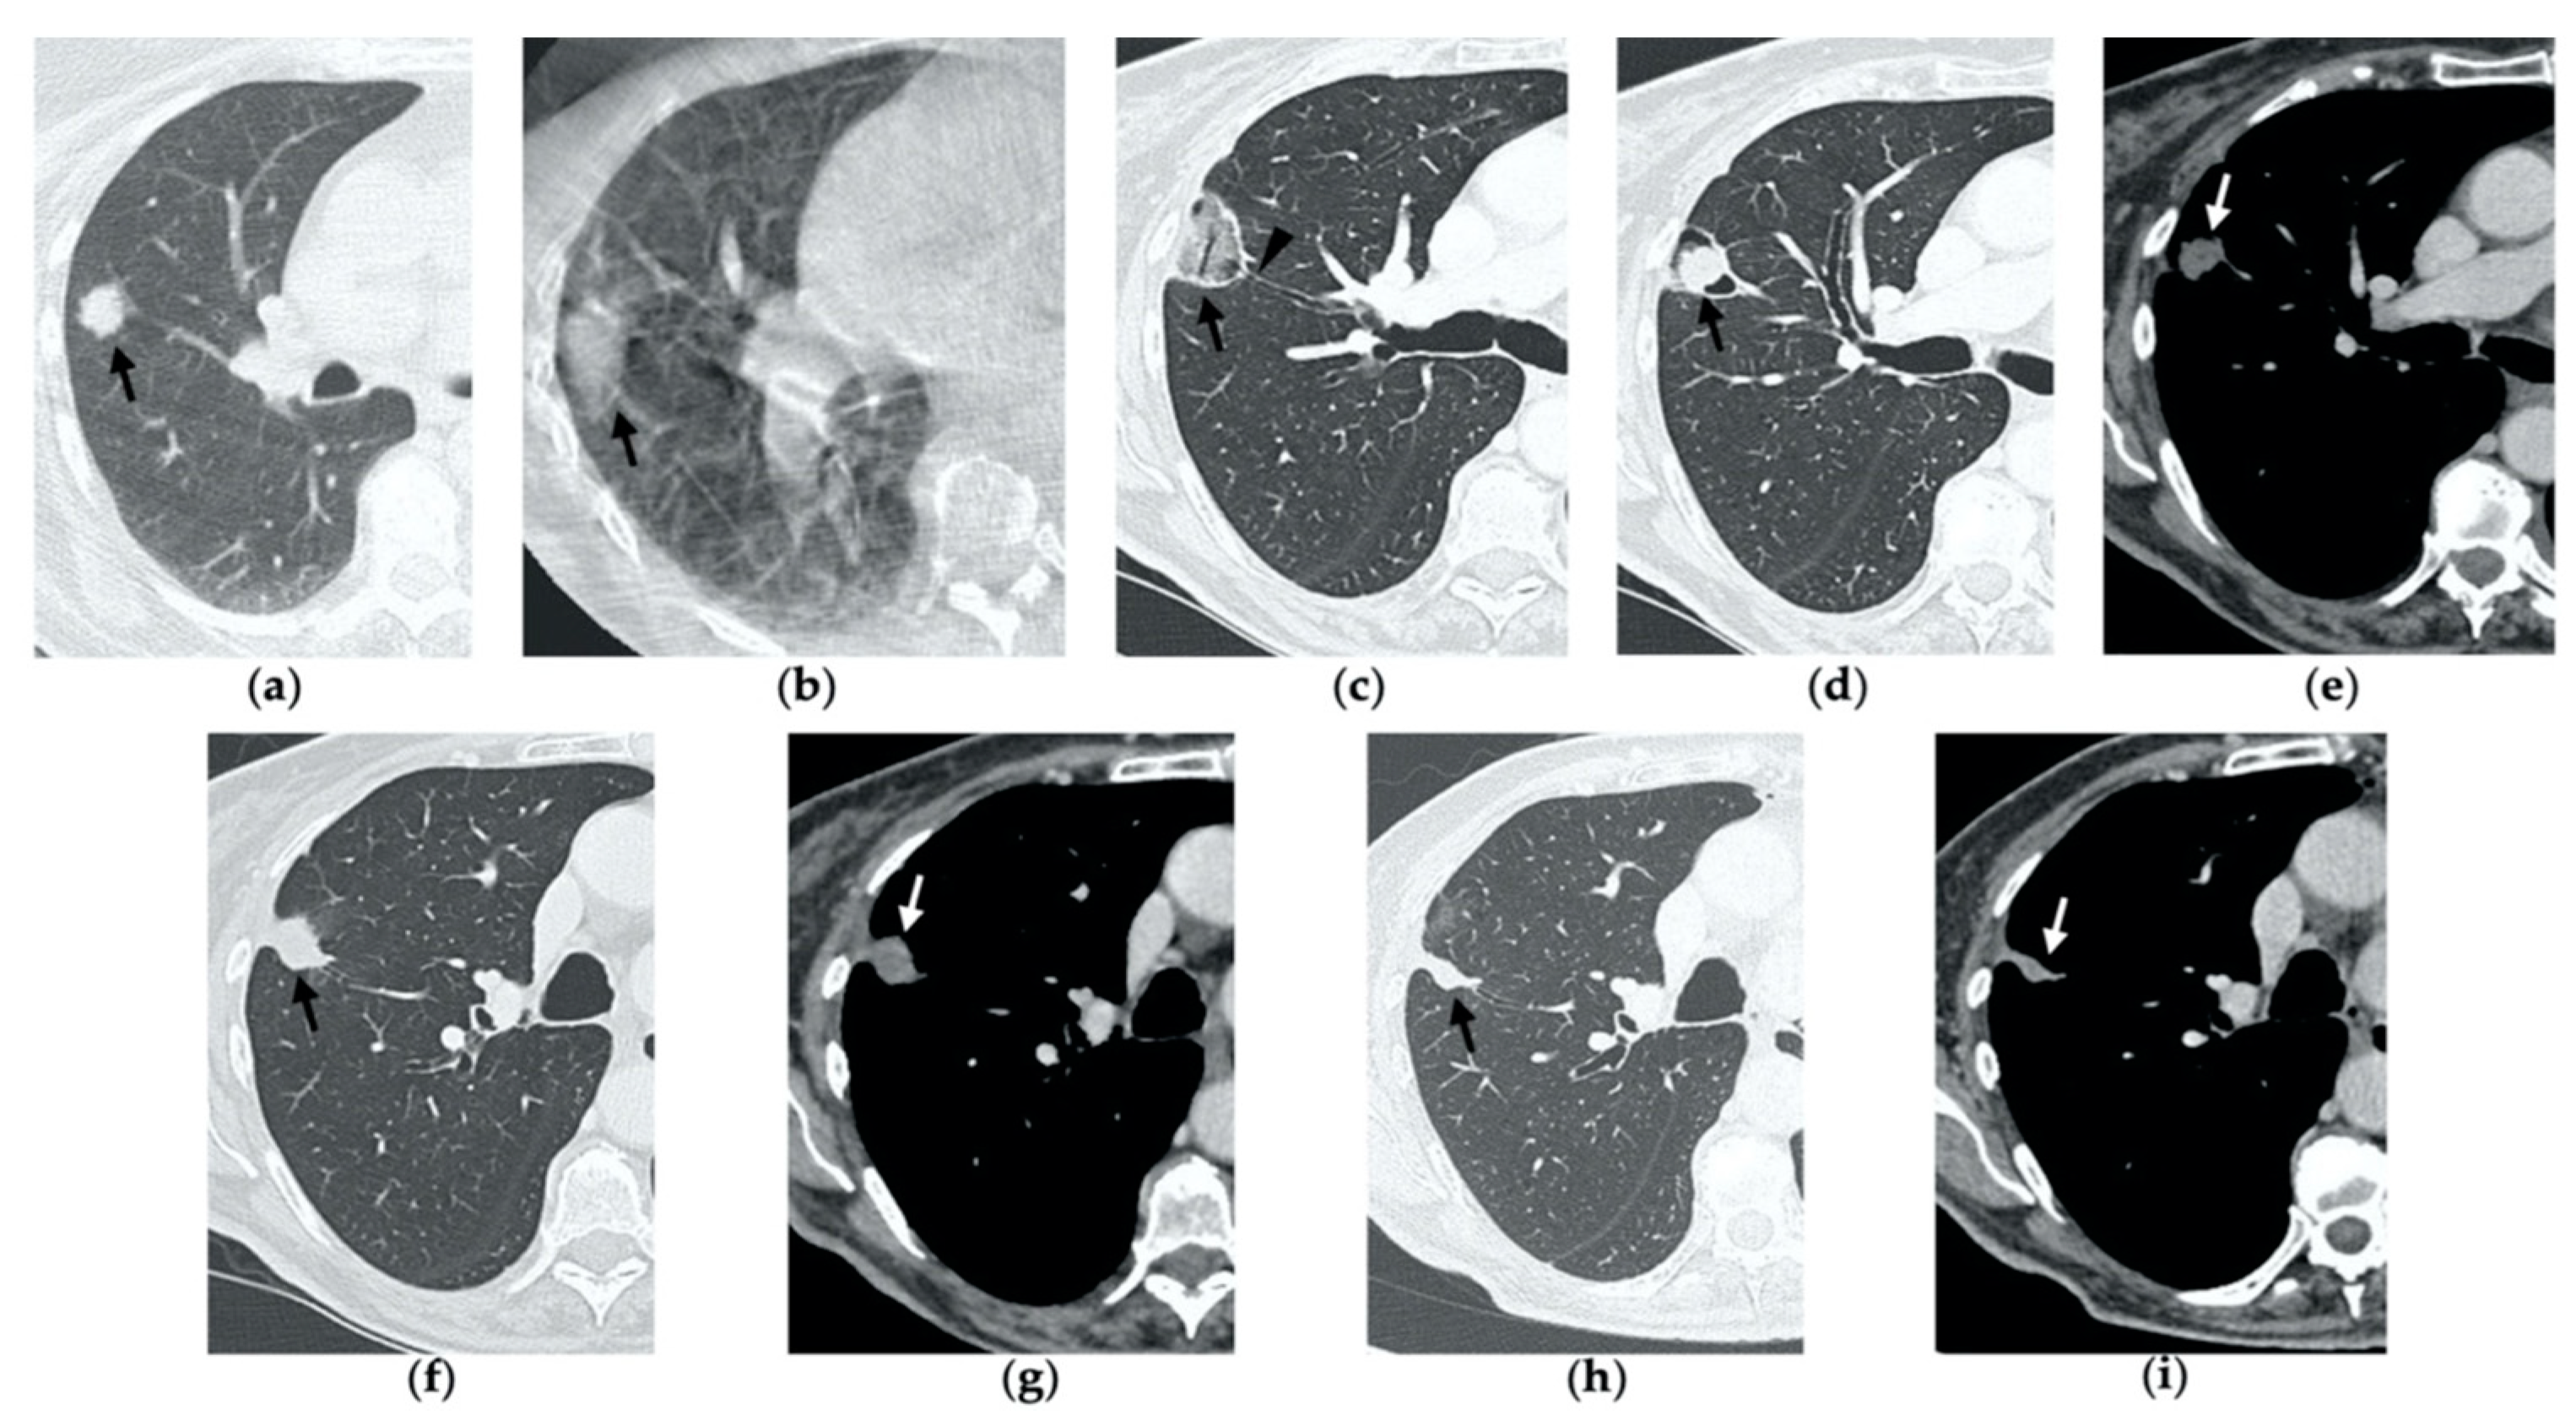

Figure 1. 74-year-old man with a pulmonary metastasis from bladder urothelial carcinoma. (a) Cone-beam CT image of the left upper lobe metastasis (black arrow) prior MWA. (b) Cone-beam CT image obtained post-procedure shows hazy GGO of the ablation site surrounding the treated nodule (black arrow) and a small layer of lateral pneumothorax (arrowhead). (c) Axial 1-month follow-up CT image shows a large consolidation with inner cavitation (black arrow). (d,e) Axial 3-month follow-up CT image shows resolution of the cavitation and decrease in size of the consolidation (black arrow) (d) and demonstrates peripheral mild enhancement with no central contrast material uptake (white arrow) (eg). Axial (f) and coronal (g) CT images obtained after 10 months show a residual fibrotic band (black arrow).

By the first month after MWA, the rim of parenchymal GGO has dissolved in most patients as a result of regressing parenchymal edema, inflammation and hemorrhage, and the ablation site appears as an area of consolidation with a mean diameter still larger than the preablation zone (Figure 3c,d and Figure 4c,d) [21]. It is, therefore, crucial in this phase to measure the area of consolidation by its maximum axial diameter in order to thoroughly compare it during the following phases [7]. The consolidation may demonstrate inner cavitation or a central hypoattenuating area with reduction in contrast material uptake, along with a mild peripheral enhancement layer as an expression of reactive hyperemia, which should present smooth with linear margins (Figure 1c) [7,15]. This phenomenon must be referred to benign periablational enhancement and it should be differentiated from pathological contrast uptake, which is usually more irregular and nodular-shaped [7]. It is, therefore, pivotal to perform CT before and after contrast material administration in order to adequately evaluate the enhancement features of the treated tumor. The ablation site may also show hypoattenuating bubbles or a cavity with thin walls, containing solid tissue with reduced contrast enhancement, necrotic material or air-fluid levels, and a communication between the cavitation and a bronchus may be recognized (Figure 2c–e) [7,16]. The latter being a common finding since the necrotic tissue may be evacuated through a bronchus and it should not be mistaken for rare although possible complications, such as an abscess or a broncho-pleural fistula (BPF). Unlike the normal cavitary changes of the ablation area, an abscess is a rare complication (0.5%) [20] and appears as a cavity with thick walls, irregular internal contours and air-fluid level, and must be suspected when fever and laboratory signs of infection are present [22]. Pleural changes are also common findings, especially in peripheral lesions, including pleural thickening in the region of pleura traversed by the microwave antenna, pleural retraction and effusion [15]. Reactive mediastinal lymphadenopathy often occurs at an early stage, and it should not be considered a sign of tumor progression [7,23].

On CT images obtained at 3-month follow-up, the size of the ablation zone should be the same or still larger than the baseline tumor, although it undergoes further involution compared to the early phase, as during the fibrosis process the wall thickness and the previously depicted cavities progressively decrease (Figure 1d) [7]. The attenuation of the ablated tissue decreases, as there is no more central contrast material uptake in relation to the local necrotic changes, while the peripheral benign enhancement may persist or decrease (Figure 1e). Overall, the size of the ablation area at this stage should become stable along with a decrease in wall thickness [7,8].

After 6 months, the ablation site undergoes further involution and there should not be any inner contrast enhancement, except for the persistent benign periablational area (Figure 2f,g) [7]. The previously mentioned cavities decrease in size and may completely disappear. CT images may show fibrotic scarring without contrast enhancement and mild architectural parenchymal distortion of the surrounding lung (Figure 1f,g) [24]. At this stage, small treated nodules may already show a linear fibrotic evolution on CT images (Figure 2h,i).